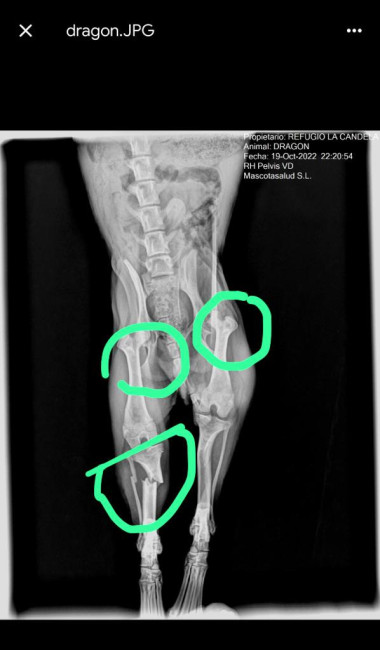

Dragon wurde angefahren. Er war knapp 1 Jahr alt zu diesem Zeitpunkt. 3 schwerwiegende Frakturen wurden operiert. Nach einer Rehabilitationsphase mit Physiotherapie wurde er genesen und glücklich vermittelt.